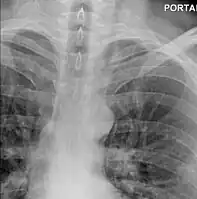

Upright chest radiography showing mediastinal air adjacent to the aorta and tracking cephalad adjacent to the left common carotid artery. This patient presented to the Emergency department with severe chest pain after eating. -